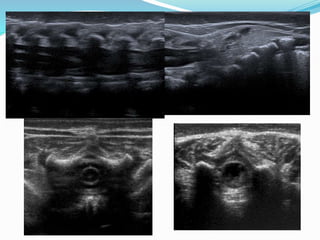

CAUDA EQUINA

Movimiento

(Modo M)

Simetría

Asimetría =

anomalía (masa

ocupante de

espacio)